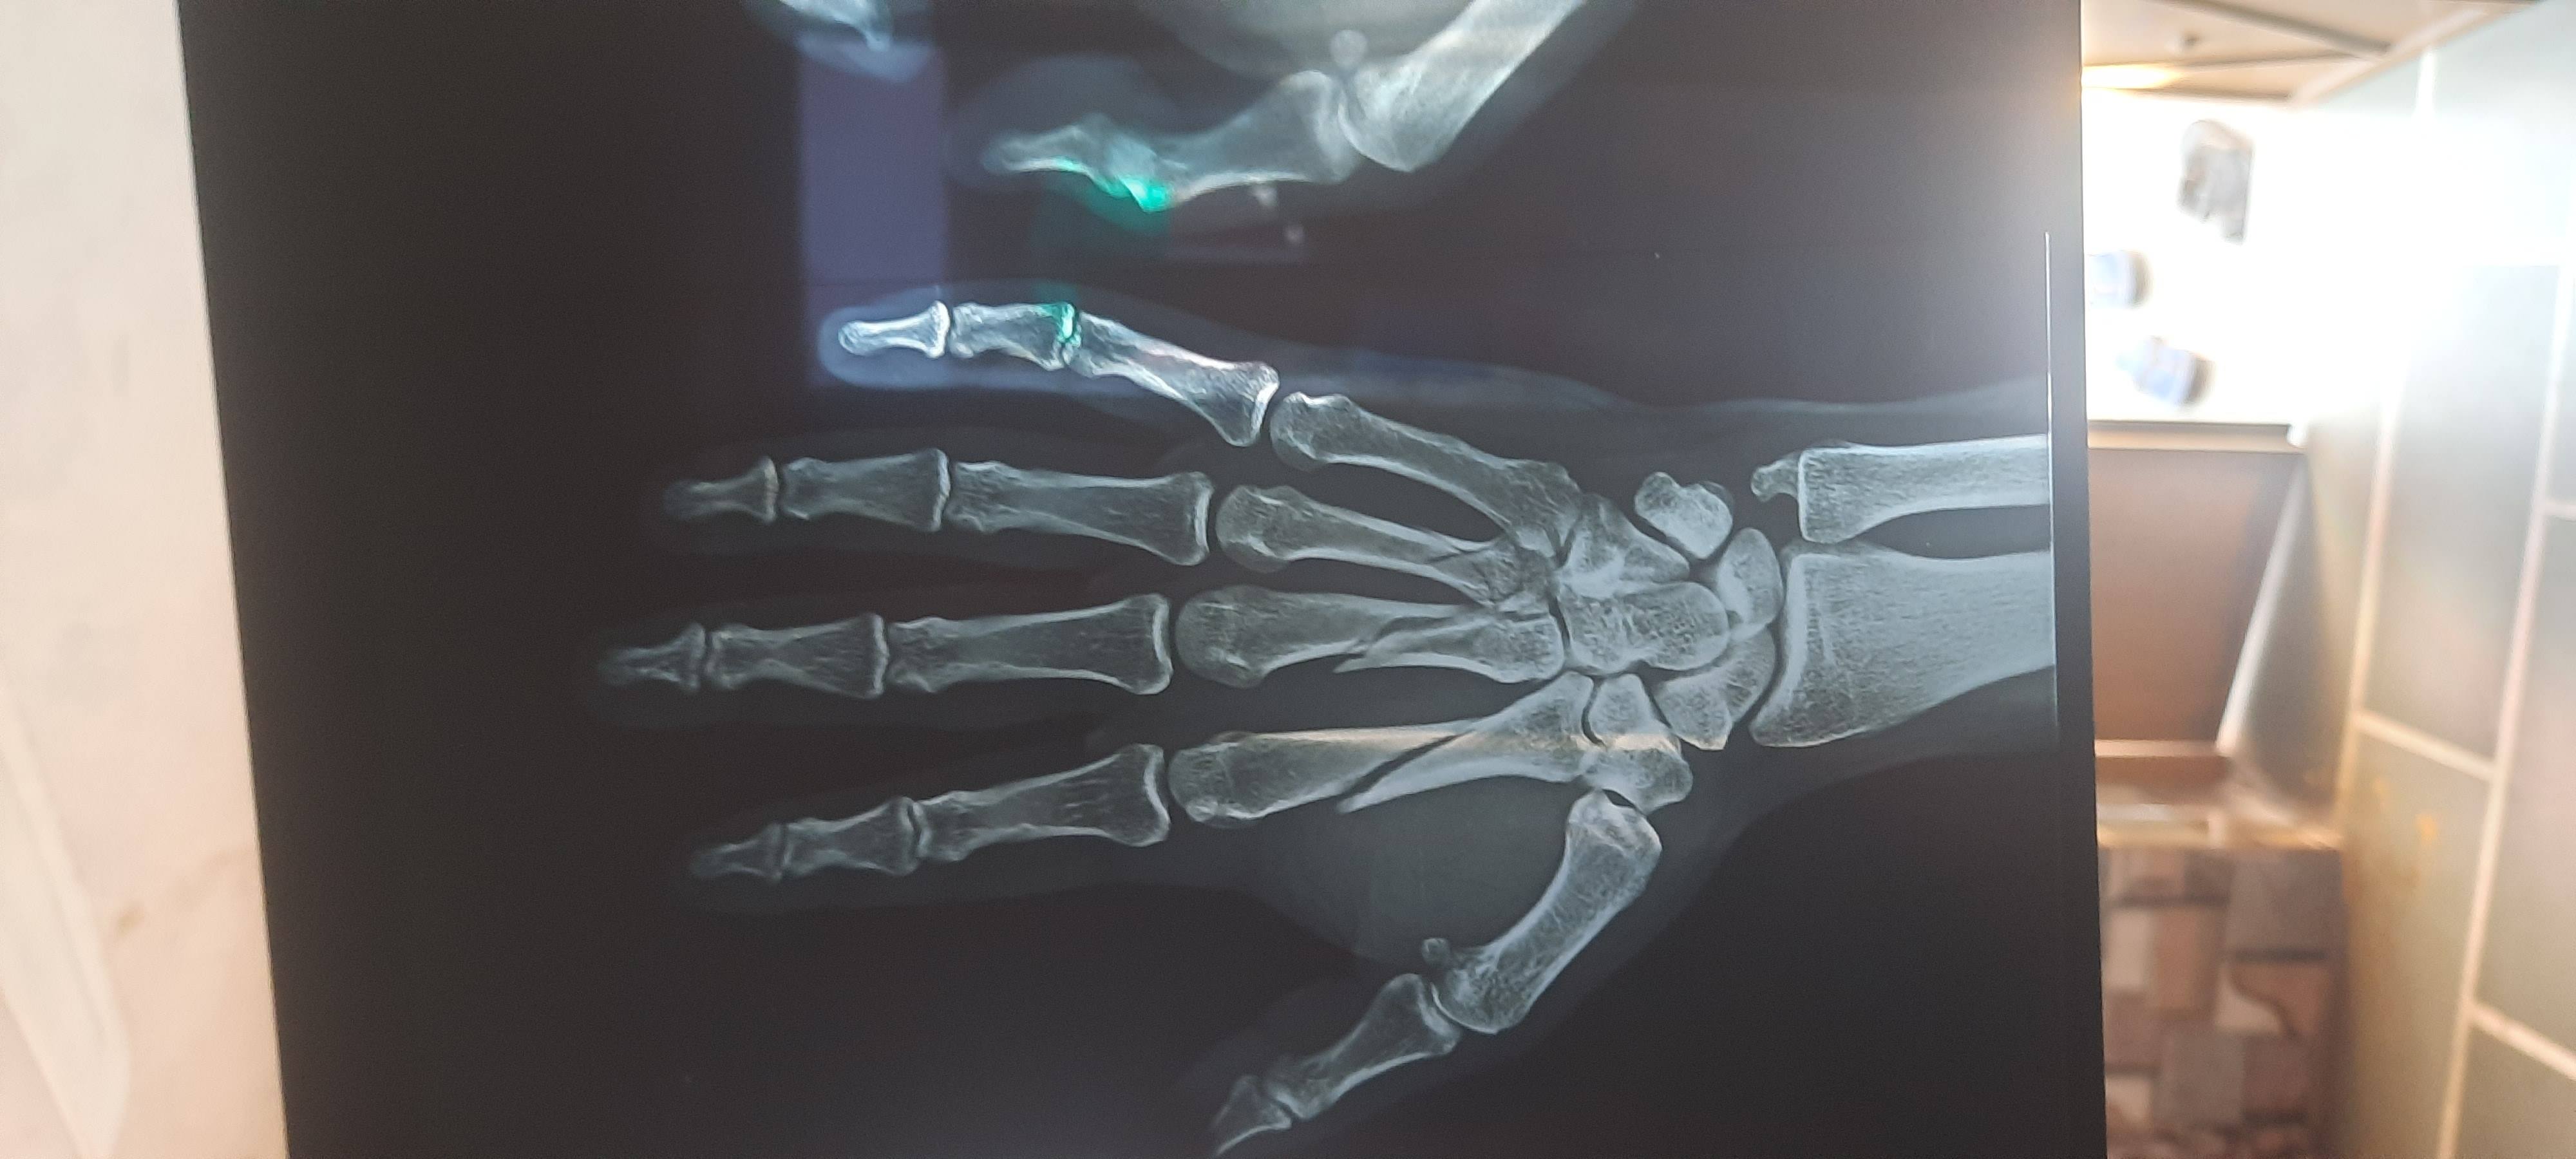

Dheeraj Kumar odichya